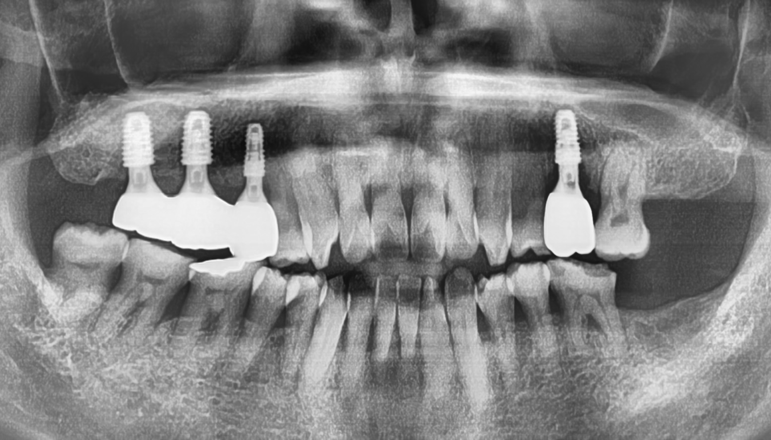

『최종 완성, 1년 소요』

양측으로 다 4개의 임플란트를 심었고, 여기에 상악동 거상술 및 뼈이식에 따라서

회복을 하는 기간을 포함하여 총 1년이 소요 되었습니다.